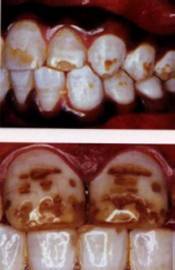

Six types of fluorosis (Source: Fluoride Free, Ireland):

• Type 4: [Top] The teeth erupt chalky white. Later the tooth displays surface damage i.e. brown discolouration. [Bottom] Further, brown pits arise due to excessive fluoride. This damage is irreversible.

• Type 5: [Top] The enamel damage effects more teeth. Unsightly and weakened teeth result. [Bottom] Most of enamel has been lost from tooth surface. The protective layer is gone.

• Type 6: [Top] Barely any normal enamel left. All teeth are severely effected. [Bottom] The teeth have many pits and holes. Now these teeth are more likely to decay and crumble.